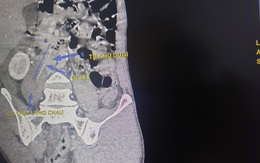

Thanh niên 28 tuổi nhập viện trong tình trạng đau âm ỉ vùng bụng phải kéo dài nhiều ngày. Kết quả chụp CT phát hiện dị vật là cây tăm xỉa răng dài 5,5cm đâm xuyên thành manh tràng bệnh nhân này.